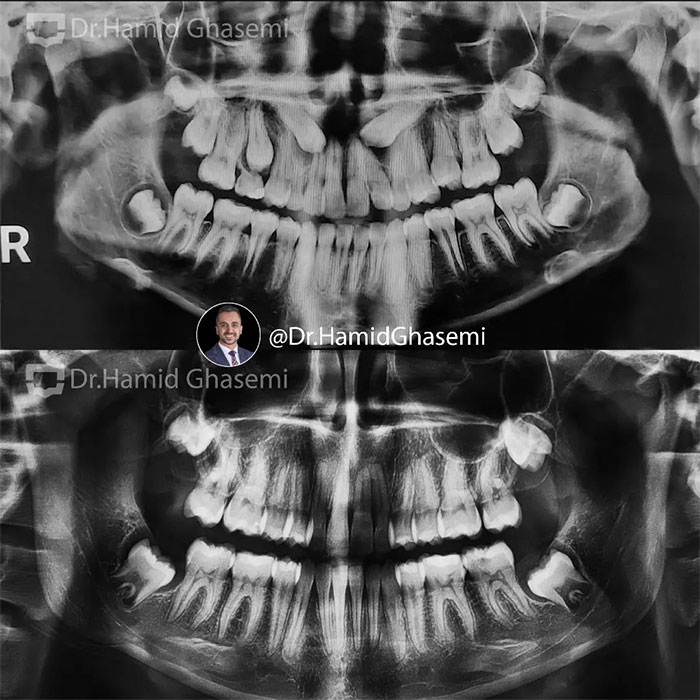

یک کیس خیلی جالب با مشکل جلوزدگی متوسط فک بالا و پایین (Bimaxillary dentoalveolar protrusion ) همراه با نهفتگی دوطرفه دندانهای نیش فک بالا. درمان با کشیدن دندان های نیش نهفته فک بالا و دندانهای پرمولر اول پایین انجام شد. تغییرات مثبت و قابل توجه در پروفایل و حالت لبهای بیمار پس از درمان و کسب اکلوژن کلاس ۱ ایده آل همچنان که دندانهای پرمولر اول بالا جایگزین دندانهای نیش نهفته در فک بالا شدند کاملا مشهود است.

This was such an amazing case with moderate bimaxillary dentoalveolar protrusion plus impacted bilateral upper canines. The case was treated by extraction of upper impacted canines and lower 1st premolars. Significant profile change achieved while upper 1st premolars substituted for upper canines properly with a solid perfect class 1 dental occlusion.